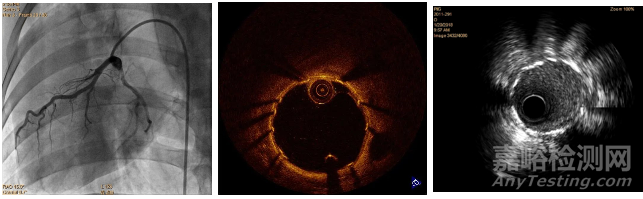

心臟冠脈支架植入需要特定導(dǎo)管室,以及影像設(shè)備,試驗(yàn)開始時(shí)從股動(dòng)脈穿刺,插入穿刺鞘和導(dǎo)絲,經(jīng)鞘管沿導(dǎo)絲將導(dǎo)管送至冠狀動(dòng)脈開口位置,造影觀察冠狀動(dòng)脈情況,沿導(dǎo)絲送入球囊支架系統(tǒng)擴(kuò)開支架,經(jīng)OCT探查管腔情況,完成植入。

植入過程如圖3所示,植入后造影圖如圖4所示。

圖4 植入影像學(xué)檢查